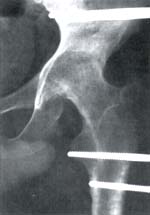

| Fig. 4a Paciente 20 años con artrosis séptica cadera izquierda, secuela herida por arma de fuego. Fase inicial compresión. ![]() |

Fig. 4 Control postoperatorio 2° mes. Procedimiento adicional, transporte óseo fémur ipsilateral por fractura abierta grado III. ![]() |

Fig. 4c Finalización del tratamiento. Fusión articular completa, 4° mes

postoperatorio